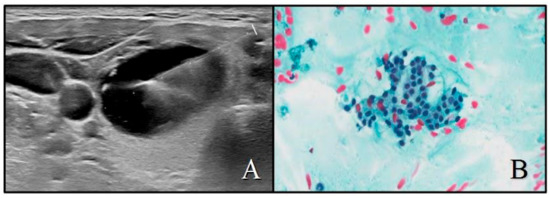

2.2. Ultrasound Evaluation

2.3. Cytopathology and Histopathology